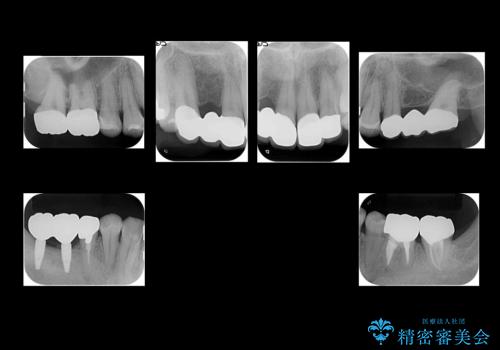

右下奥歯二本はインプラントにしました。(横浜桜木町歯科院長 大元先生による)

また、銀歯はすべてやり直しを行い、セラミックでやり替えを行いました。

前歯の治療を先に行い、見た目を改善した後、奥歯の治療を行いました。